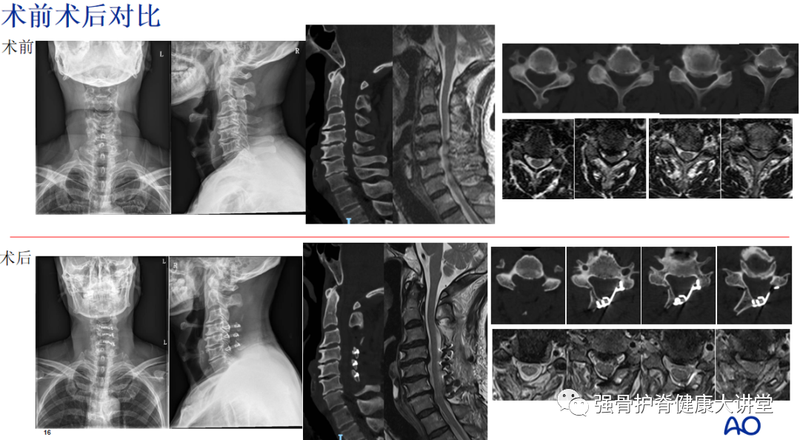

?2021年11月68歲的張先生,因雙下肢乏力10余年來我院就診,伴行走不穩(wěn),腳踩棉花感。經(jīng)保守治療后無明顯緩解,遂來我院就診,來時(shí)患者雙下肢乏力,行走不穩(wěn),腳踩棉花感,自訴雙大腿拉扯感,偶有左上肢外側(cè)拇指食指麻木疼痛,雙手不自覺震顫,雙膝關(guān)節(jié)活動(dòng)受限。查體:左側(cè)椎間孔擠壓試驗(yàn)(+),雙側(cè)霍夫曼征(+)、巴氏征(+),雙下肢肌張力亢進(jìn)?;颊哳i部CT、MR提示:C3/4、C4/5、C5/6、C6/7椎間盤突出并椎管狹窄。結(jié)合癥狀、體征及影像學(xué)檢查,可診斷為:1.脊髓型頸椎病?2.發(fā)育性頸椎管狹窄(C3-7椎間盤突出并椎管狹窄)3.神經(jīng)根型頸椎?。–5、6左側(cè)椎間孔狹窄并神經(jīng)根受壓)4.腰椎管狹窄癥(L2-S1椎間盤突出并椎管狹窄)。目前保守治療無效,建議手術(shù)。與患者充分溝通病情、排除手術(shù)禁忌癥后,經(jīng)科室專家討論,江曉兵教授帶領(lǐng)團(tuán)隊(duì)為患者行頸椎后路單開門椎管減壓術(shù)+顯微鏡下C5、6神經(jīng)根管減壓術(shù)。術(shù)后患者癥狀明顯改善,滿意出院。隨訪半年影像學(xué)隨訪半年患者術(shù)后癥狀緩解,功能基本恢復(fù)正常。任輝主治醫(yī)師點(diǎn)評(píng):該患者以雙下肢乏力伴行走不穩(wěn)10余年為主要癥狀就診,結(jié)合影像學(xué)和體格檢查,發(fā)育性頸椎管狹窄、頸椎間盤突出、黃韌帶增生導(dǎo)致的頸椎椎管狹窄、脊髓壓迫是上述癥狀的主要原因,同時(shí)考慮患者有左上肢外側(cè)拇指食指麻木疼痛的癥狀,需要重視C5、6左側(cè)椎間孔狹窄導(dǎo)致的相應(yīng)神經(jīng)根受壓。因此,在手術(shù)方案制定上面,可考慮頸椎后路單開門椎管減壓術(shù)+顯微鏡下C5、6神經(jīng)根管減壓術(shù)。江曉兵教授總結(jié):頸椎后路單開門術(shù),一方面基本不破壞頸椎后方穩(wěn)定結(jié)構(gòu),通過擴(kuò)大椎管容積以解除脊髓后方的壓迫,使脊髓后移躲開其前方壓迫,從而達(dá)到減壓效果;另一方面通過顯微鏡技術(shù)完成椎間孔切開、解除神經(jīng)根管狹窄。術(shù)后臨床癥狀得到明顯改善,隨訪半年患者癥狀消失,功能恢復(fù),獲得我們術(shù)前規(guī)劃的如期效果。